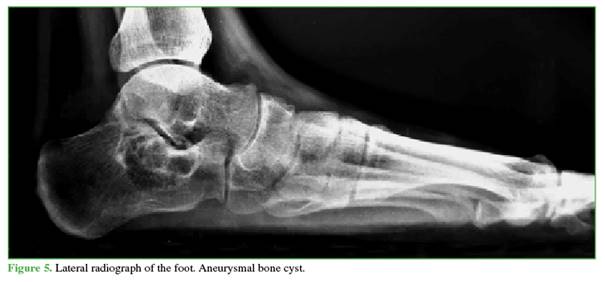

The differential diagnoses of a benign polylobulated calcaneal tumor included a simple bone cyst (Figure 4), an ABC (Figure 5), or an intraosseous lipoma (Figure 6).